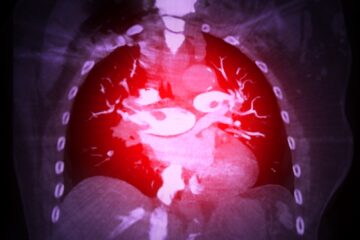

Prieširdžių virpėjimas, dar vadinamas AFib, – tai dažniausia širdies ritmo sutrikimo forma. Ši būklė sukelia nereguliarų širdies viršutinių kamerų plakimą ir gali padidinti rimtų komplikacijų, kaip insultas ar širdies infarktas, riziką.

Dažniausiai prieširdžių virpėjimas pasireiškia dieną, tačiau nemažai žmonių naktį taip pat patiria nemalonių pojūčių. Dėl to ne tik blogėja miego kokybė, bet ir apsunksta ilgesnio poilsio galimybės.